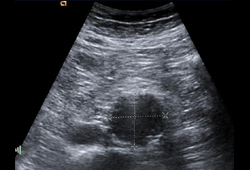

- Ecografía aórtica